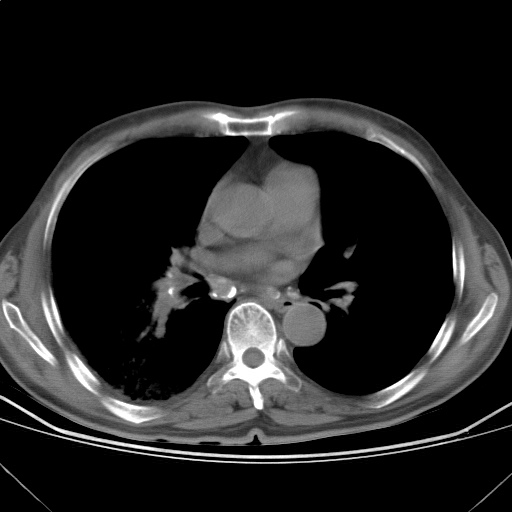

以下是引用随光逐影在2009-5-1 13:53:00的发言:[br]考虑为:1)两肺血行播散型肺结核;2)右肺下叶炎症感染。3)右侧胸膜增厚。